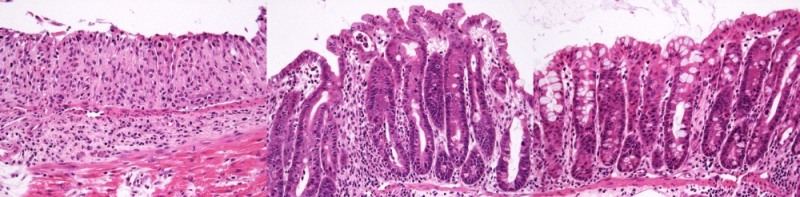

그 결과, 개발한 신약후보물질 FBCA201이 대식세포에서 LPS처리에 의한 NO생성의 억제와 염증성 사이토카인 발현을 억제함으로써 지나친 염증반응을 조절할 수 있음을 확인했고 동물의 장조직에서 대장상피세포에서의 TNFα 처리에 의한 접착단백질의 발현을 억제함으로써 염증세포와의 결합을 조절하는 항염 효능을 입증했다.

특히 염증성 장질환 동물 모델 실험에서 장길이 감소, 장점막 손상, 배변이상 등의 실제 증상의 치료효과를 현재 크론병의 1차 치료제로 사용되는 설파살라진 및 5-ASA 과 대조하여 실험한 결과 기존 치료제 투여량의 20% 용량을 투여하였음에도 더 우수한 효과를 보이는 것으로 확인됐다.